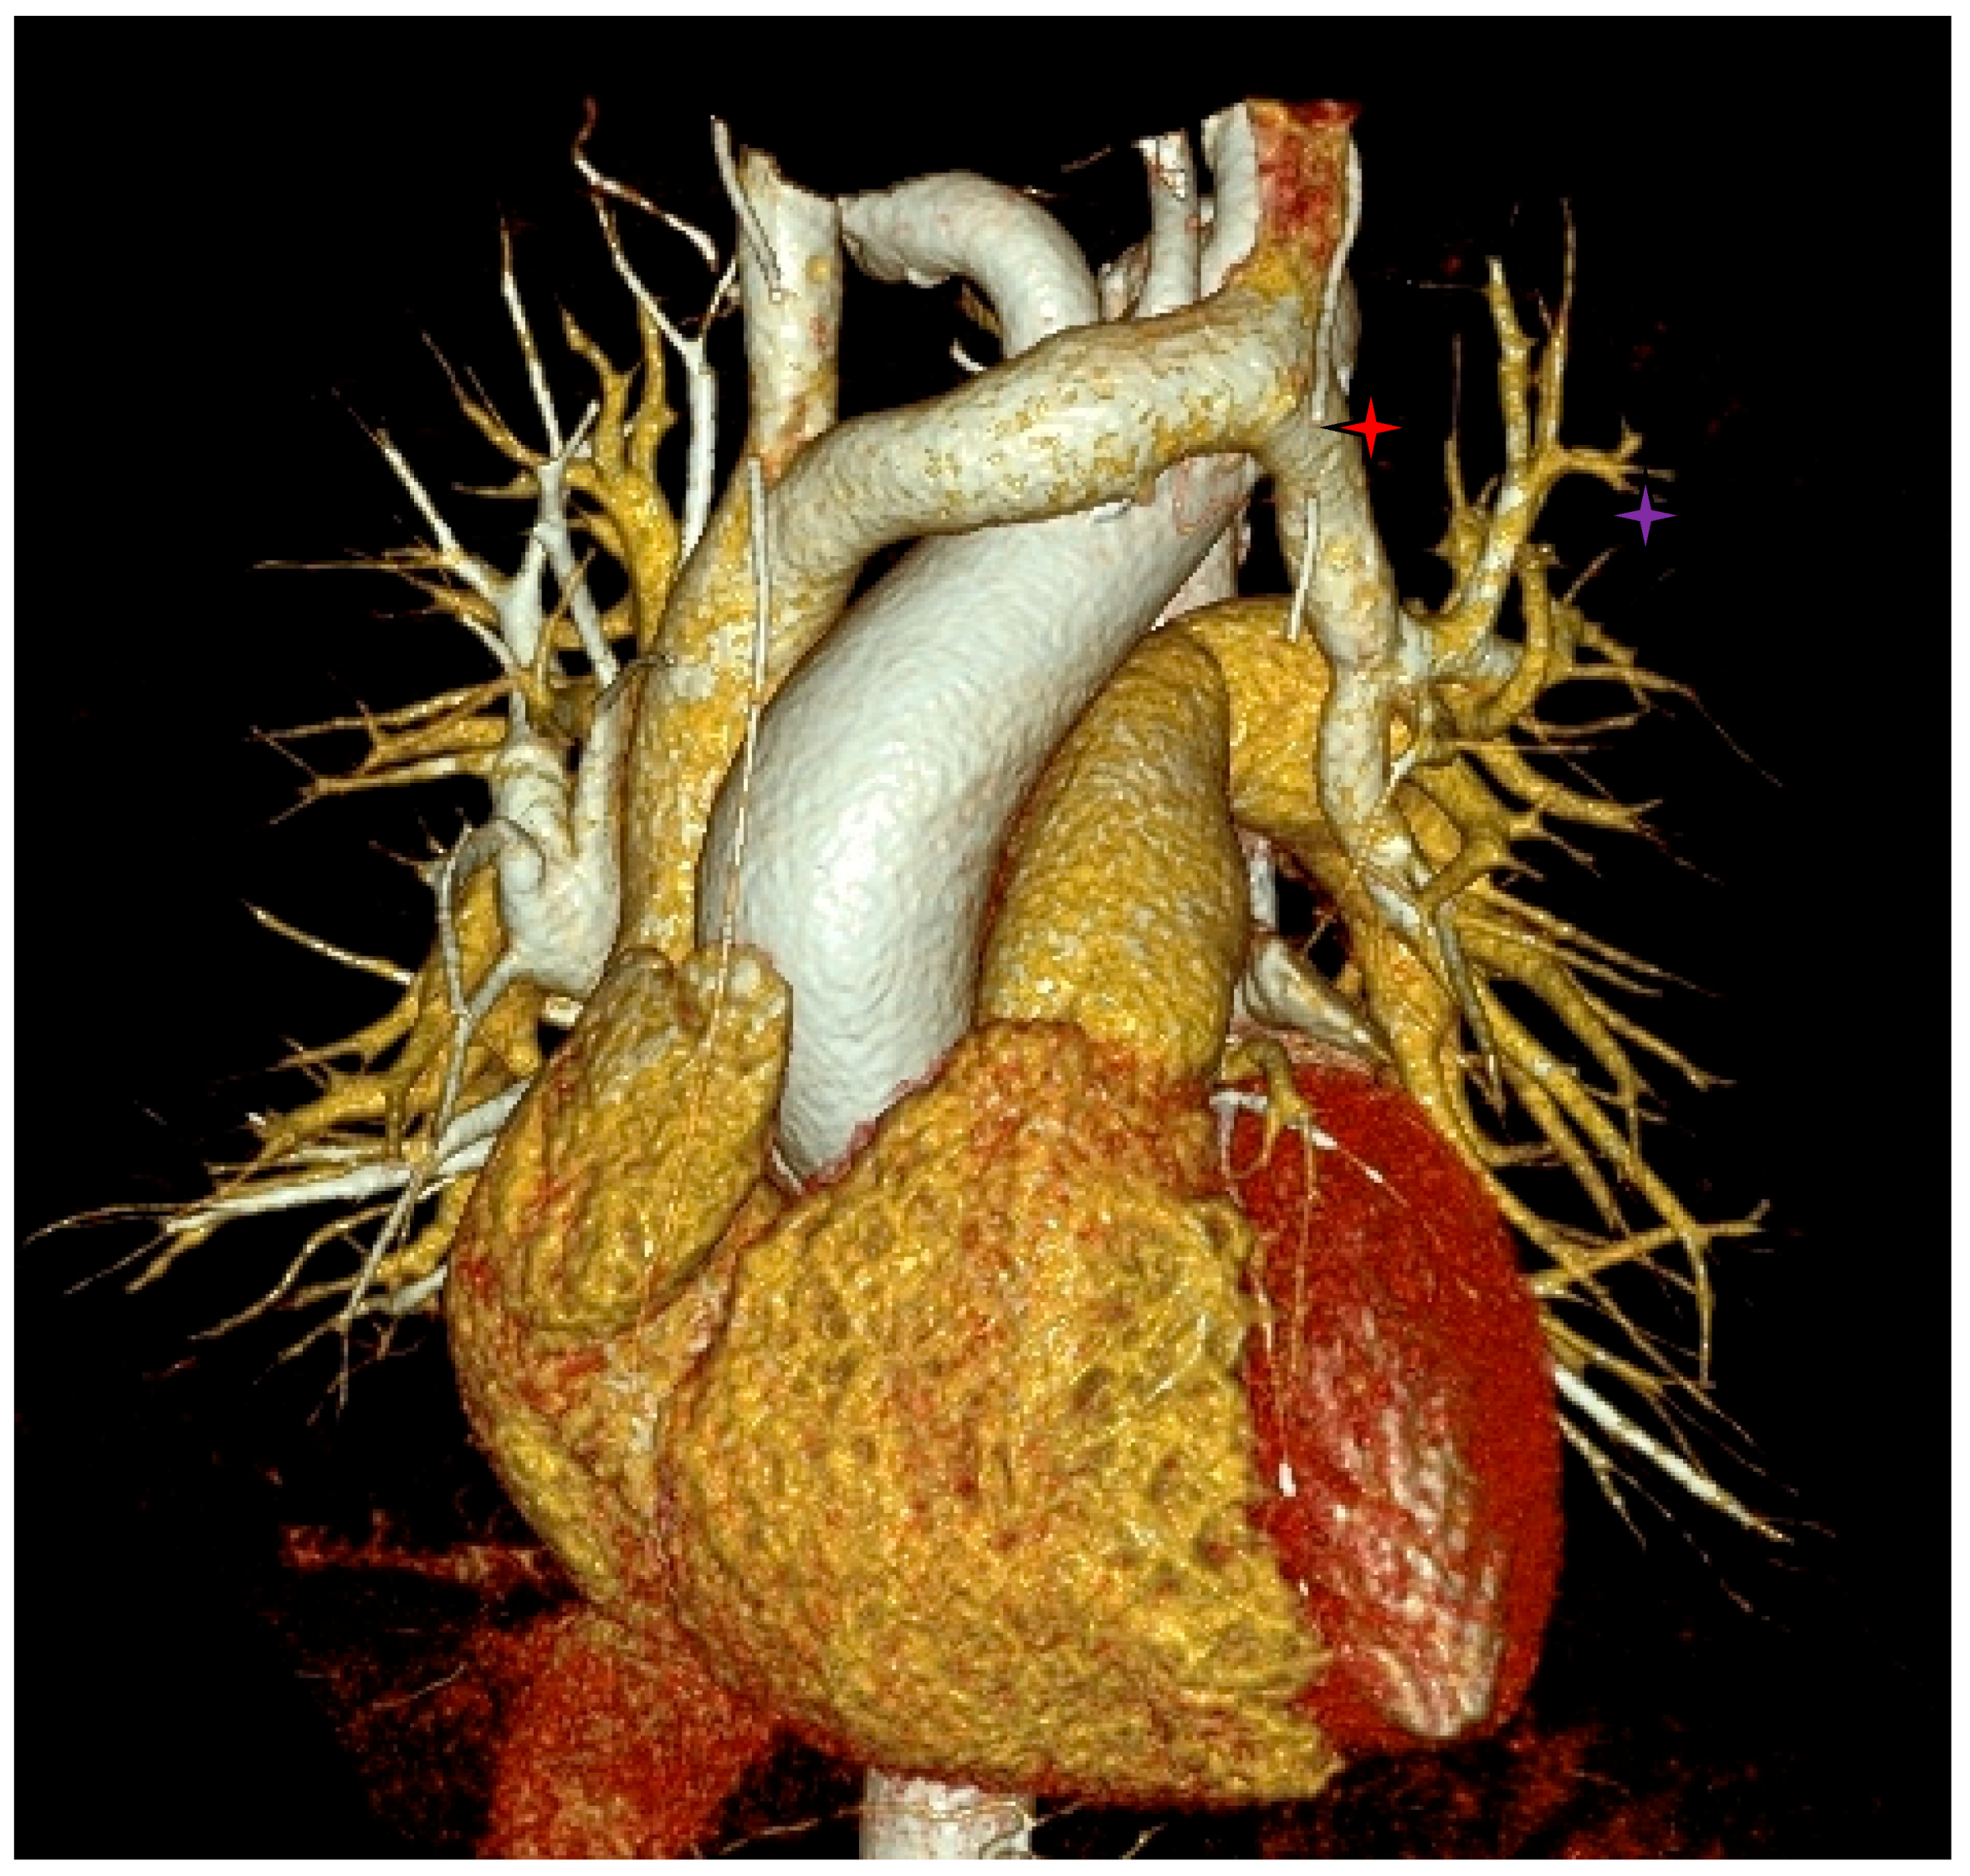

- Incidental vascular finding No. 2: Right Aortic Arch.